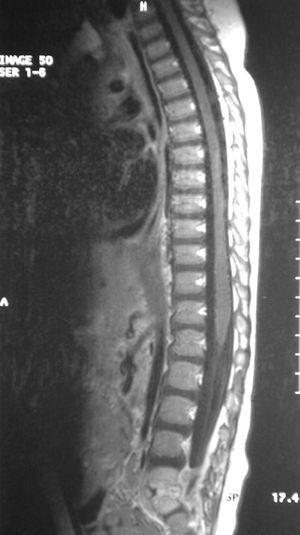

La resonancia magnética (RM) ayuda a diferenciar entre alteraciones óseas vertebrales y patología de la cadera o de la médula espinal. En nuestro caso las imágenes en T1 (fig. 3) con contraste con gadolinio demostraron un realce anormal del disco y de las partes adyacentes de los cuerpos vertebrales y las imágenes en T2 (fig. 4) mostraron una señal anormal y disminución de la altura del disco y unos platillos irregulares, cambios compatibles con espondilodiscitis L5-S1.

Figura 4. Imagen en T2, disminución de altura del disco y platillos irregulares.